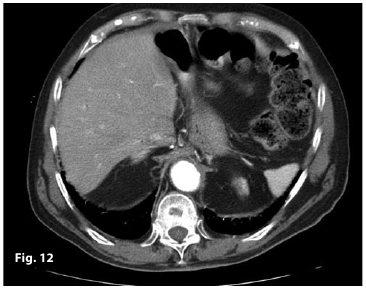

Figure12